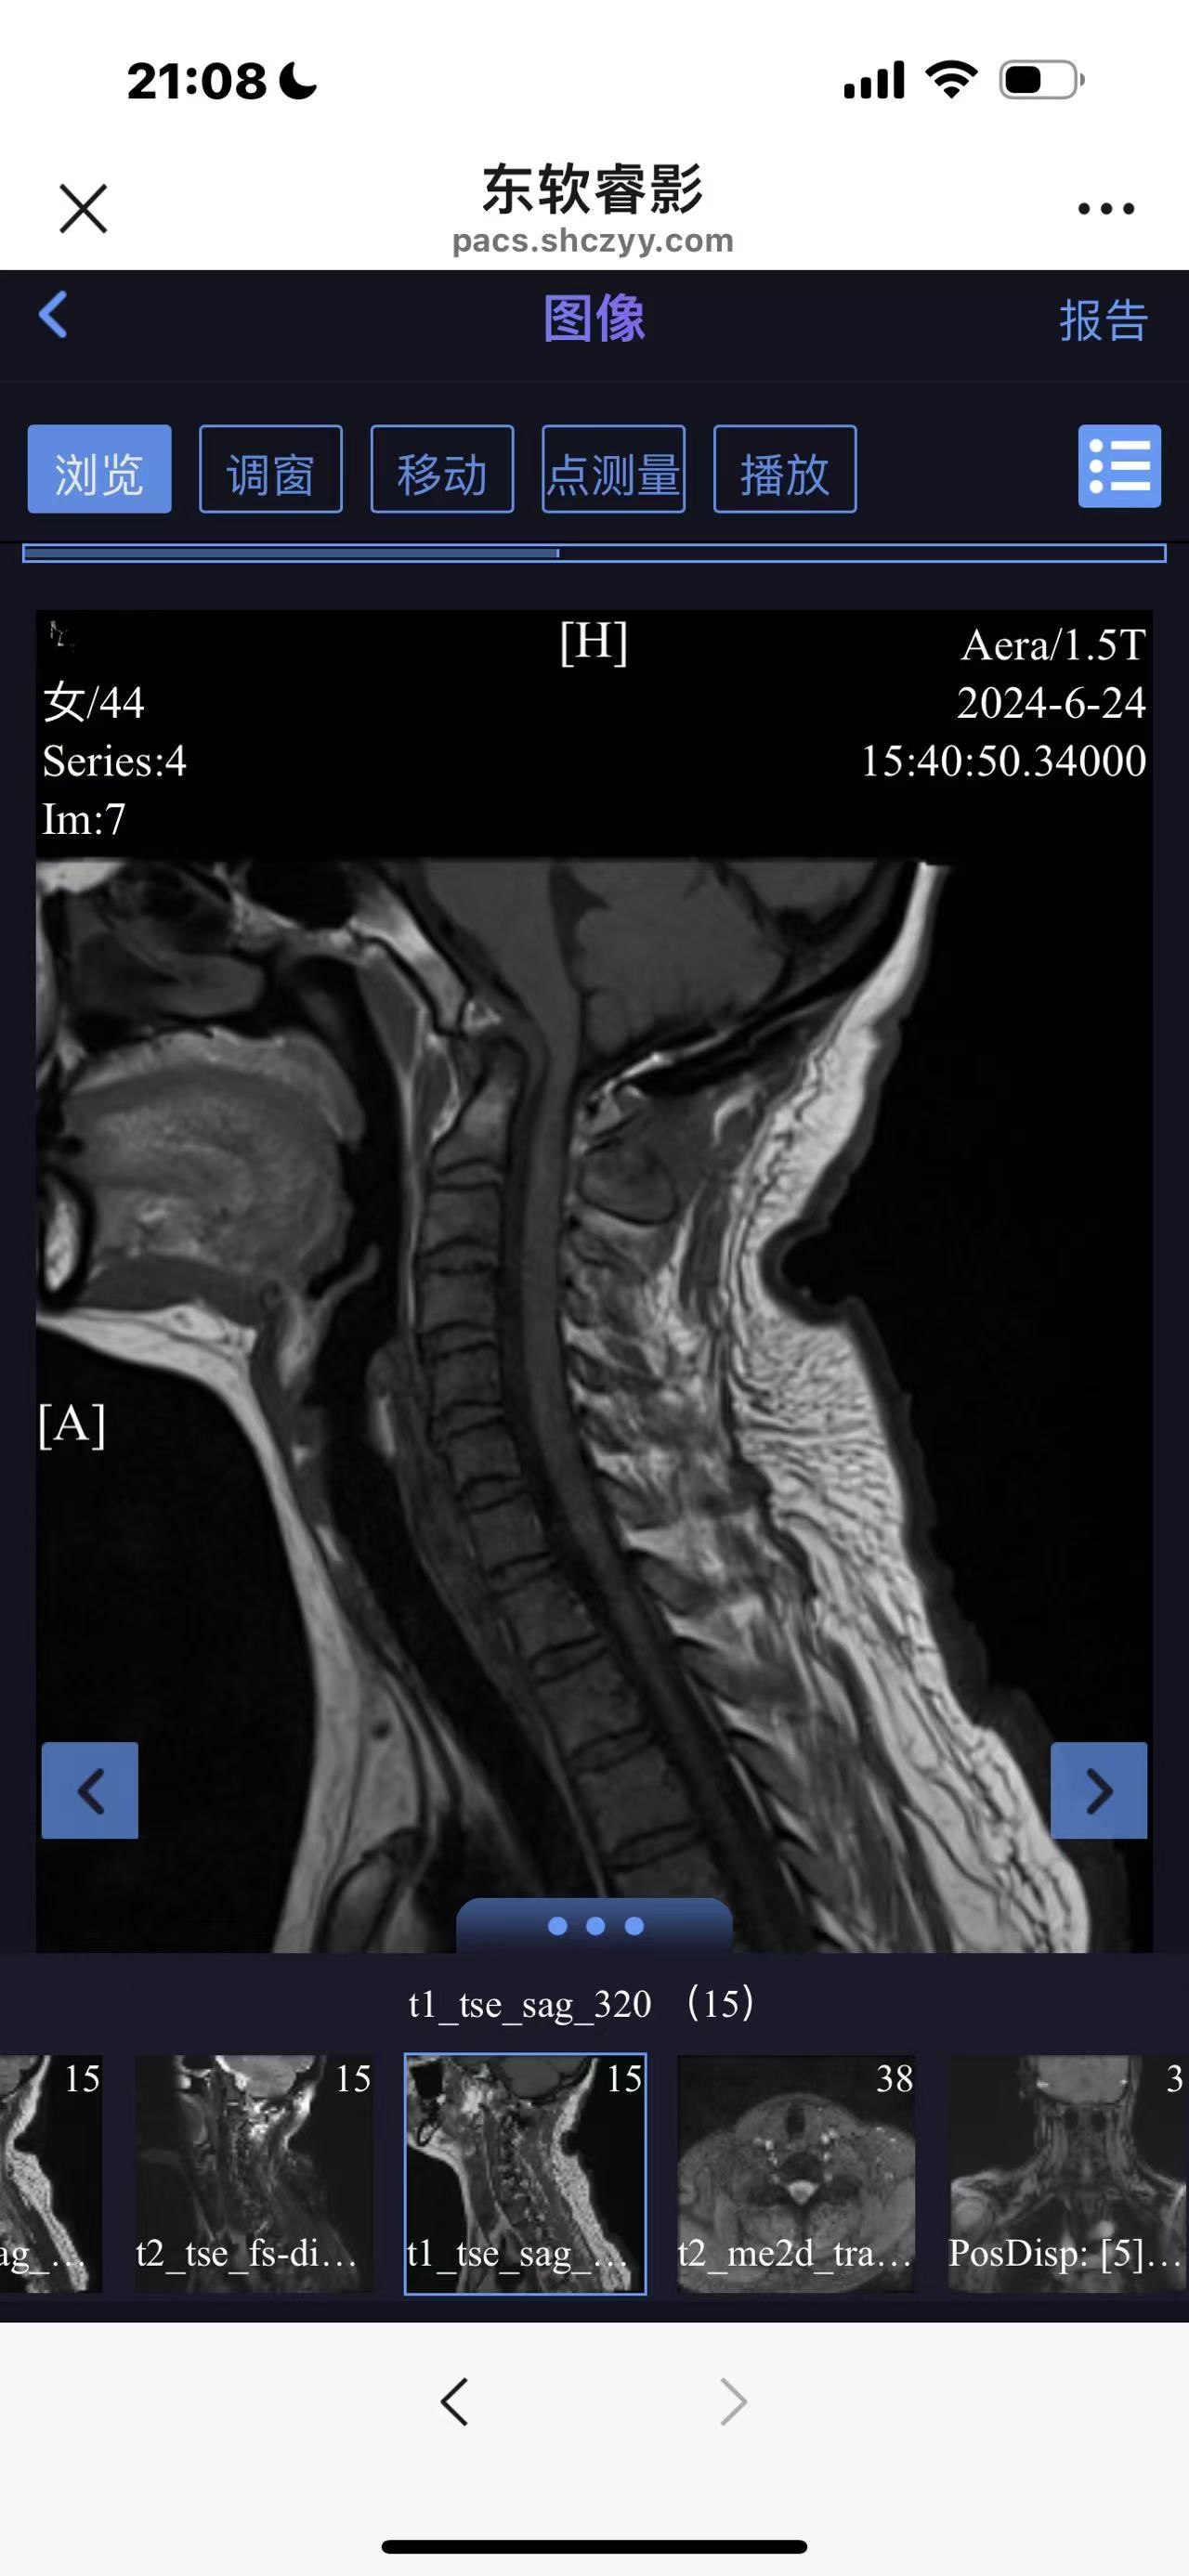

• 诊断:寰枢椎脱位

• 术后状况:没有复位

• 术后影像: